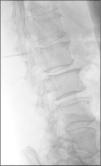

Clinical caseA 67-year-old male with a history of type 2 diabetes mellitus and lower back pain irradiating to both legs, predominantly the right, neurogenic claudication of both legs and weakness in both feet for 15 months. Physical examination revealed hypoesthesia in the right L5 dermatome, increased myotatic reflexes in both legs with Babinski sign and 4/5 power in the psoas and quadriceps bilaterally. Central and lateral stenosis of the spinal canal could be seen on magnetic resonance imaging at lumbar level from L3-L4, L4-L5, as well as the presence of a cystic lesion with regular limits, from T12 to L2. The lesion was hypointense in T1-weighting and hyperintense in T2-weighting, characteristically homogeneous with the cerebrospinal fluid; no contrast enhancement was observed on the MRI (Fig. 1). The compression of the conus medullaris and the dural sac was notable in T12-L1 and L1-L2 respectively and bilateral foraminal stenosis (Fig. 2), at the same levels due to expansion of the cyst. Given these signs, we decided to perform an evacuatory lumbar puncture targeting the spinal extradural cyst in space L1-L2 guided by fluoroscopy (Fig. 3), in order to decompress the nerve elements on which the cyst had an expansive effect. After the procedure, the patient's myelopathic syndrome improved, he had normal osteotendinous reflexes in both legs, and there were no bilateral Babinski reflexes. However, the patient continued to have neurogenic claudication and radicular pain in both legs, therefore one month after the evacuatory puncture a minimally invasive approach with microscope and tubular retractor system was undertaken through the midline for segments L3-L4 and L4-L5, and the narrow lumbar canal was decompressed. This achieved complete improvement of his symptoms.